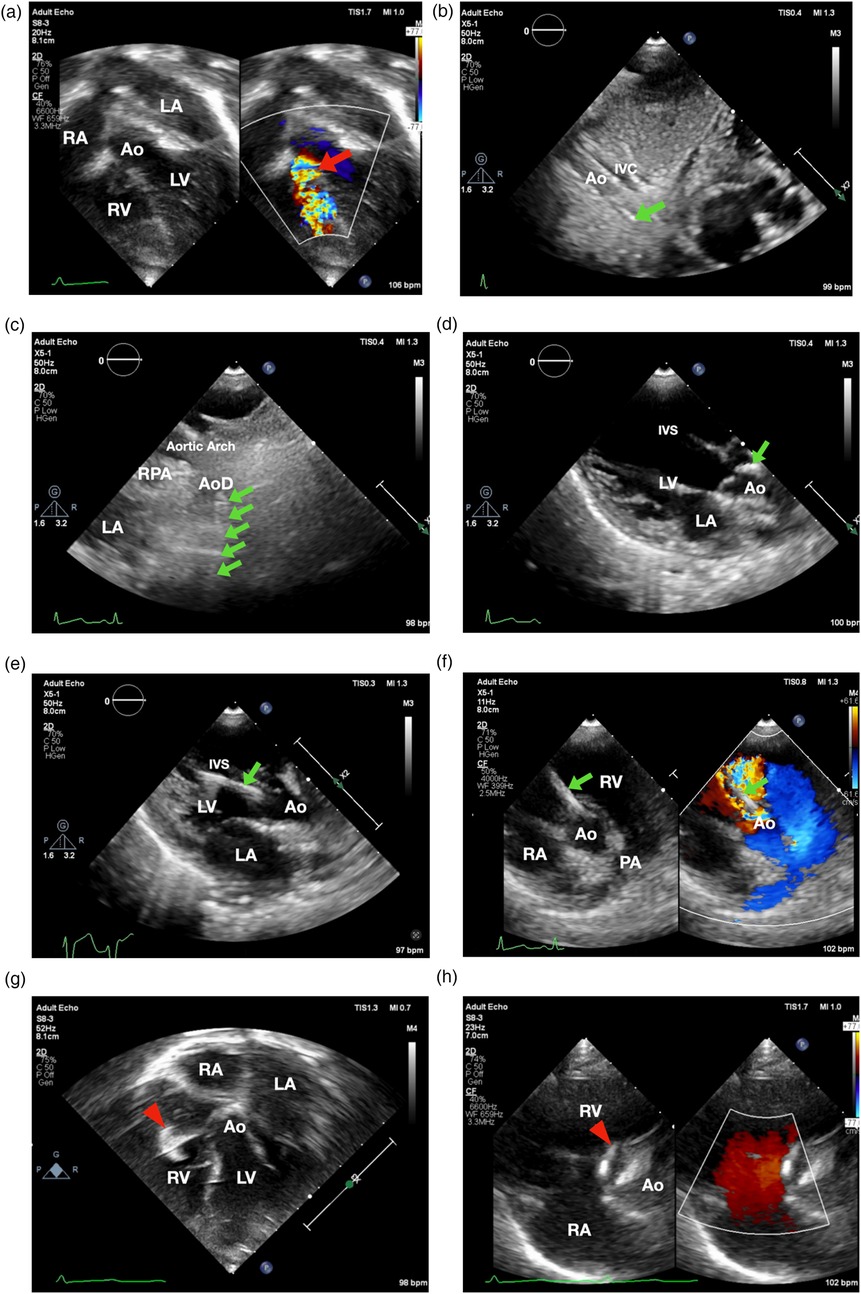

The patient underwent the procedure under sedation. Preprocedural apical 5-chamber view revealed a subaortic ventricular septal defect (VSD) with a membranous septal aneurysm (MSA), left-to-right shunt, with VSD exit diameter of 3.8 mm, and an inlet diameter of 6–7 mm (Figure 1a). There was an adequate distance between the VSD and the tricuspid and aortic valves. Mild mitral regurgitation was noted without evidence of aortic regurgitation. Based on these findings, percutaneous VSD closure was planned using a retrograde transarterial approach with TTE-only guidance.

Figure 1. Transthoracic echocardiographynnn-guided only subaortic VSD closure in infants. (a) Apical 5-chamber view showed smallest VSD diameter 3.8 mm (showed by the red arrow). (b) 3.5/5F Guiding JR catheter with soft hydrophilic wire were entering descending aorta in subxiphoid 12 o'clock view (indicated by the green arrow) (c) suprasternal short axis view. (d) Guiding catheter was then positioned just above the aortic valve. (e) Catheter entered LV as shown in parasternal long axis view. (f) 3.5/5F Guiding JR catheter crossed the VSD in parasternal short axis view. (g) The Konar-MF VSD Occluder (Lifetech) No.7/5 mm (indicated by red arrowhead) was deployed in apical 5-chamber view. (h) Device detachment was evaluated in parasternal short axis view showing no residual shunt. Ao, aorta; AoD, descending aorta; IVC, inferior vena cava; IVS, interventricular septum; LA, left atrium; LV, left ventricle; PA, pulmonary artery; RPA, right pulmonary artery; RA, right atrium; RV, right ventricle.

Aseptic and antisepsis were prepared in the left and right femoral regions. The right femoral artery was punctured, and a 4/5F slender sheath was inserted. Heparin (800 IU) was administered intra-arterially. A 3.5/5F JR guiding catheter was advanced via the descending aorta, aortic arch, and ascending aorta into the left ventricle using the subxiphoid 12 o'clock view (Figure 1b), suprasternal short axis view (Figure 1c), parasternal long axis view in which the catheter was positioned just above the aortic valve (Figure 1d) and pressure monitoring, with the assistance of a 0.035” Terumo soft hydrophilic wire. The guiding catheter was used to cross the VSD from LV to RV using parasternal long axis view (Figure 1e) and parasternal short axis view (Figure 1f). Hemodynamic measurements showed left ventricular pressure of 80/16 mmHg, right ventricular pressure of 20/6 mmHg, and descending aortic pressure of 71/37 mmHg (mean 49 mmHg). Left ventricular oxygen saturation was 98%. Prophylactic intravenous cefuroxime (400 mg) was administered.

A 5F delivery cable and a Konar-MF VSD Occluder (Lifetech) size 7/5 mm were introduced through the guiding catheter and positioned within the defect. The low-pressure disc was deployed in the right ventricle as shown in inverted apical 5 chamber view (Figure 1g) followed by deployment of the high-pressure disc in the left ventricle as shown in parasternal short axis view (Figure 1h).